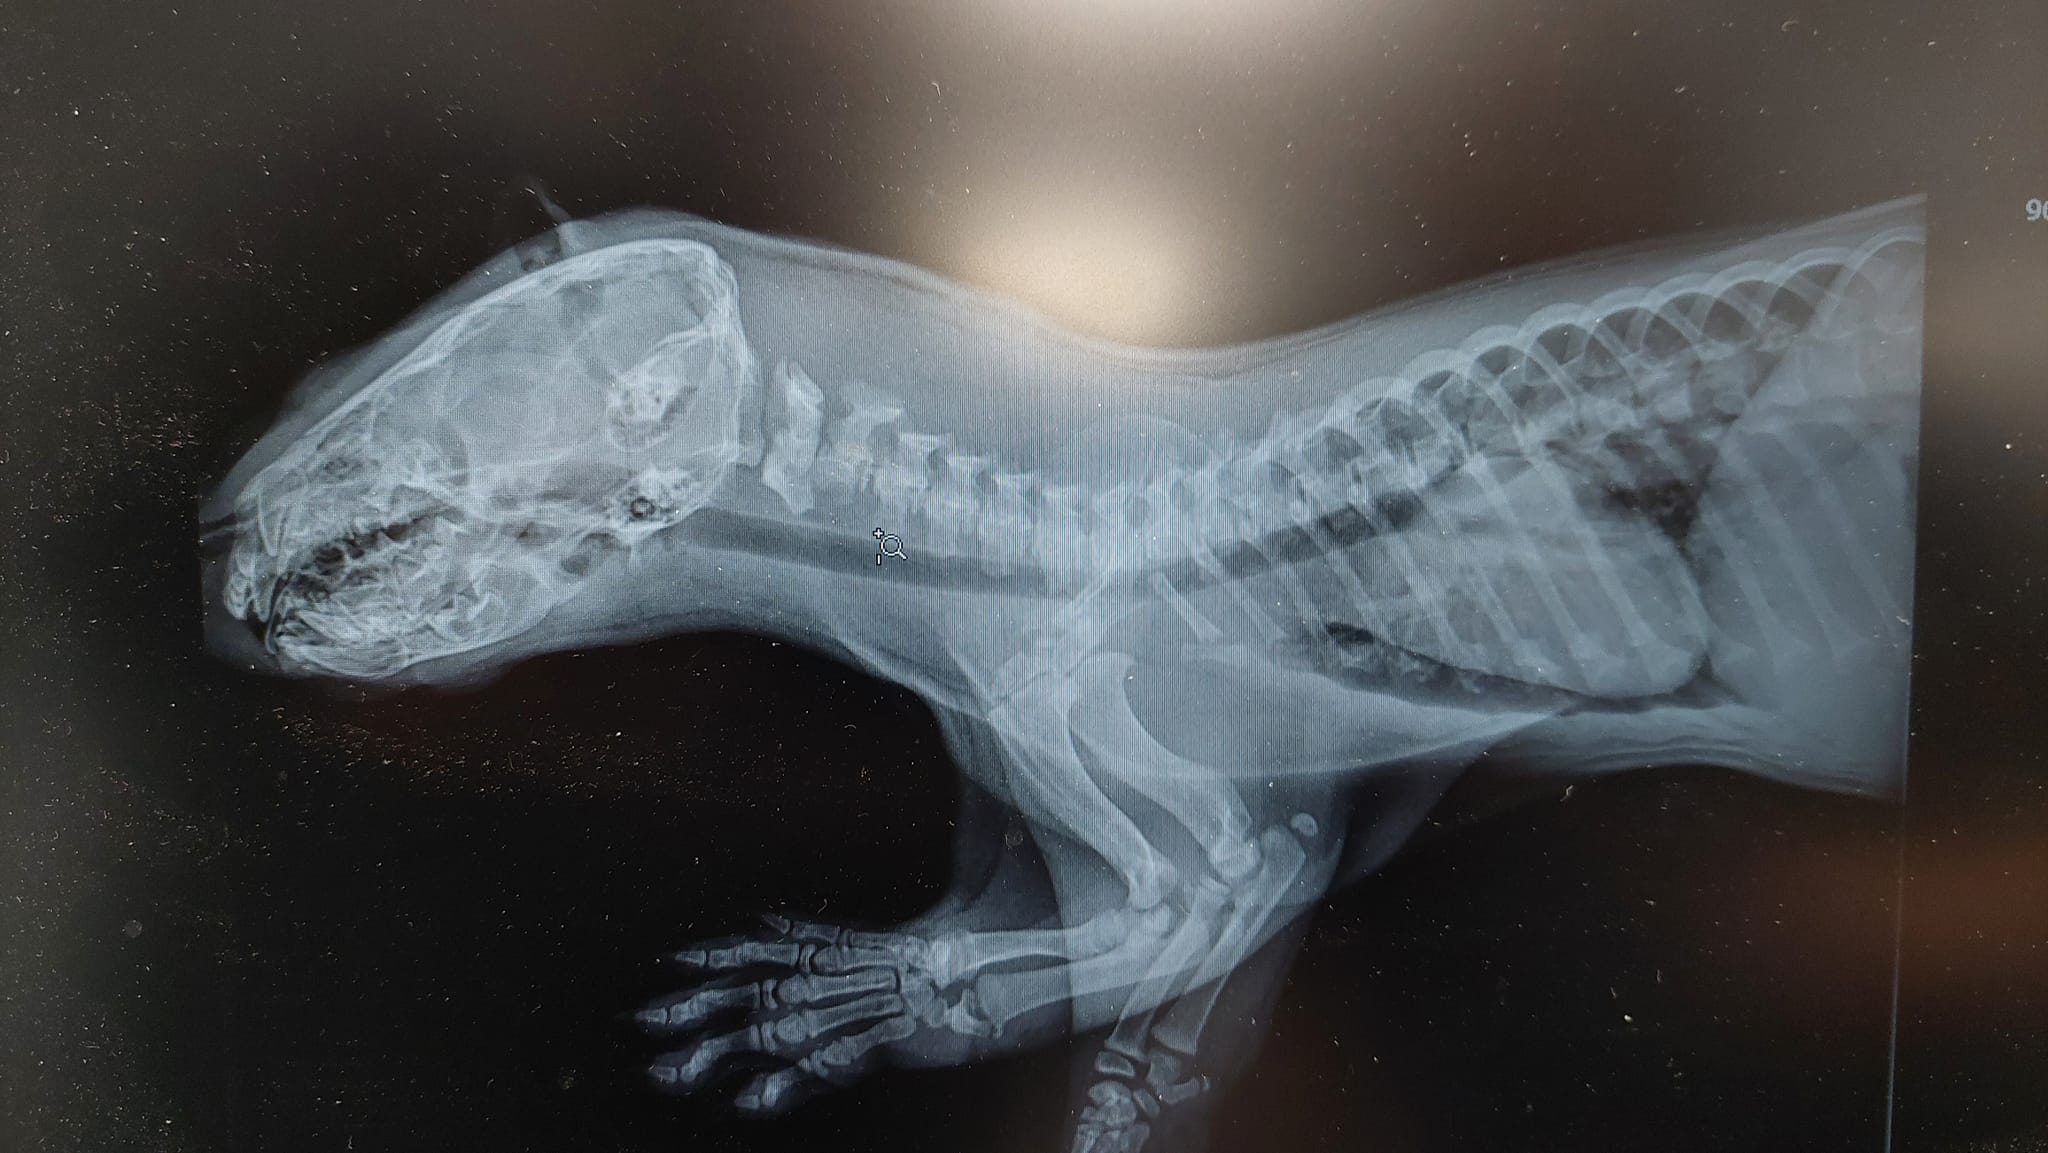

– Młoda wydra poturbowana przez psa. Uważajmy na spacerach z naszymi czworonożnymi pupilami. Na szczęście brak złamań, ale zwierzę miało obfity krwotok z nosa. Jest to tegoroczne szczenię Wydry Europejskiej (Lutra lutra) z rodziny łasicowate – głosił pierwszy komunikat specjalistów z Leśna Osada Edukacyjna w Kole – Leśny Ośrodek Rehabilitacji Zwierząt.

Dziś już wiadomo, że wydra wraca do zdrowia. – Mamy powód do radości, wydra ma apetyt. Niestety, stan jej a właściwie jego, bo to samiec, był poważny. Nie mógł przyjmować pokarmów z uwagi na uszkodzenie podniebienia. Pies prawdopodobnie chwycił za górną szczękę i ją uszkodził. Zwierzę szybko traciło siły i traciło na wadze. Jak widać na filmie, jeszcze ma problemy z gryzieniem, ale pasta rybna jest przysmakiem i wydra zjada jej spore ilości. Mamy nadzieję, że wszystko teraz już będzie dobrze i maluch za chwilę zacznie przybierać na wadze – mówią specjaliści z Nadleśnictwa Piotrków.